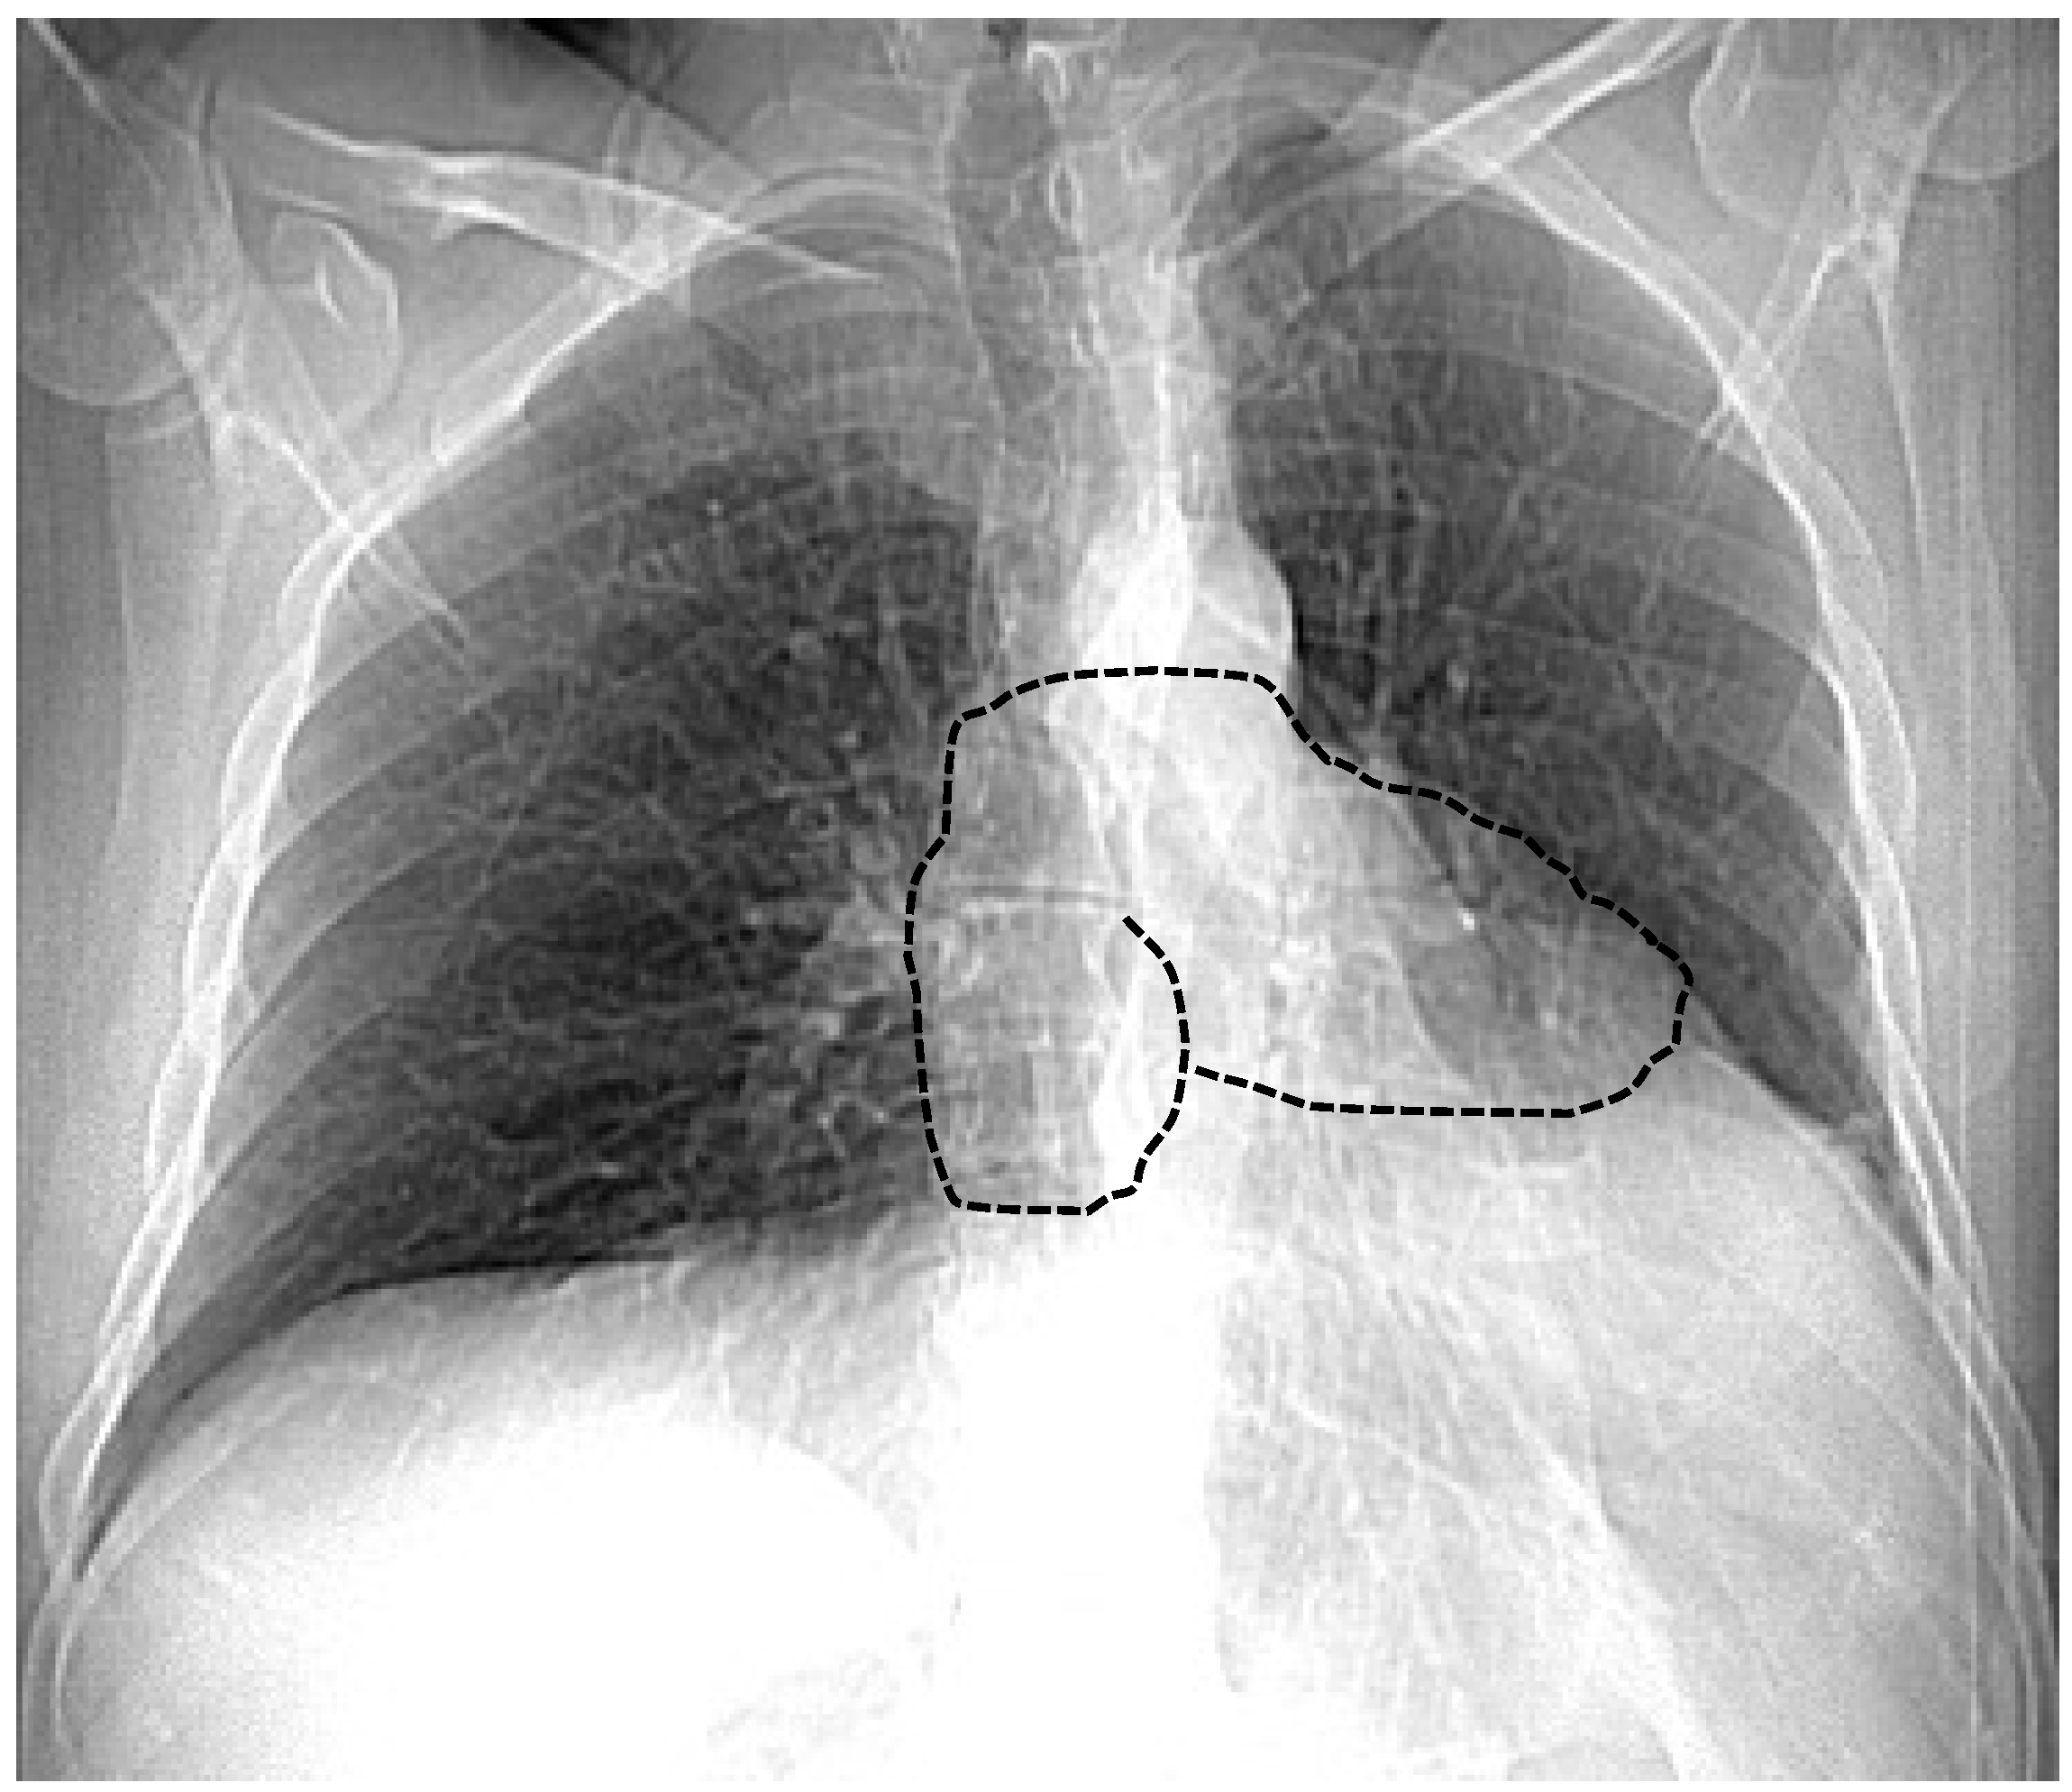

| Chest X-ray | Leftward heart displacement (Snoopy sign) Prominent main pulmonary artery Radiolucency between the heart and diaphragm | Availability Low cost Bed-side evaluation | Low sensibility Low specificity |